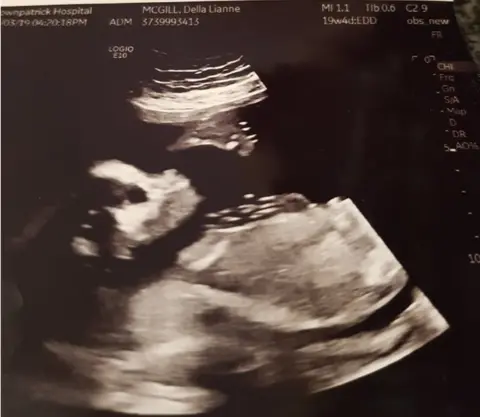

Della said: "The baby is due on 26 July - but it's a big baby and I may be induced sooner. Like its dad, it could be a rugby player in the making."

The couple do not know the sex of their baby, but cannot wait to meet their little miracle.